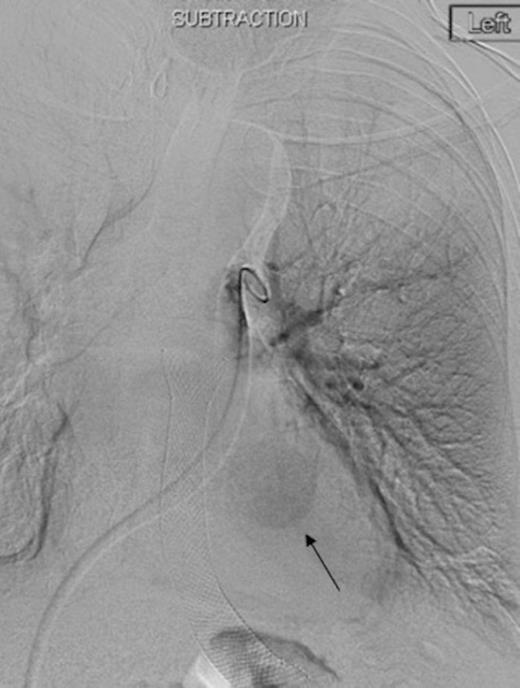

Left pulmonary artery digital subtraction angiography image demonstrating filling of left lower lobe aneurysm (arrow)

Digital subtraction angiography post deployment of the AVP 4 device in the PA branch feeding the aneurysm (arrow). No residual or collateral filling seen